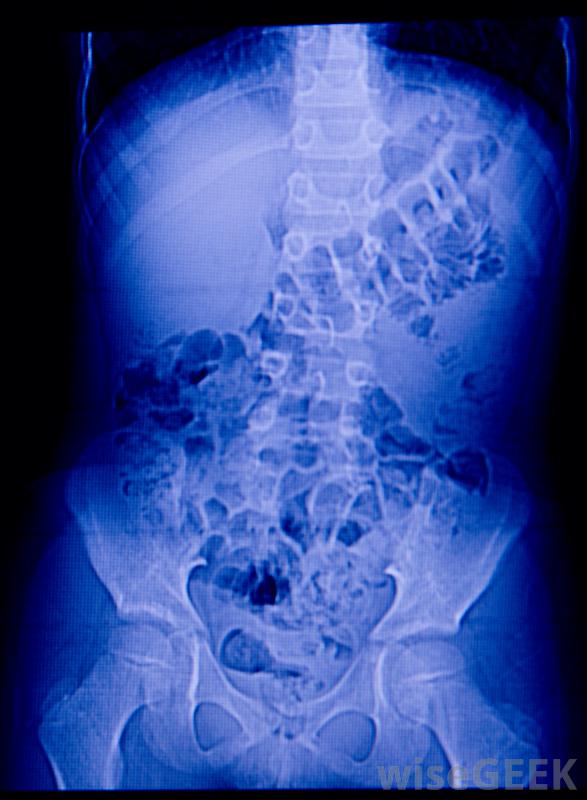

十二指腸潰瘍是一種出現在十二指腸內層,小腸上部的病變。潰瘍實質上是被細菌、胃酸或某些藥物破壞的被侵蝕組織的區域。十二指腸潰瘍最常見于老年人,雖然潰瘍可能發生在任何年齡段,但醫生通常可以用藥物或簡單的外科手術來治療潰瘍。但是,如果十二指腸潰瘍得不到治療,它會導致大量的內出血和嚴重的健康并發癥腹部X光片可顯示十二指腸異常。大多數十二指腸潰瘍是由一種特定類型的細菌引起的,稱為幽門螺桿菌(Helicobacter pylori)(H.pylori)。當細菌大量存在時,它會侵蝕十二指腸的粘膜。如果一個人經常服用非甾體抗炎藥(NSAIDs),也會出現潰瘍,吸煙和飲酒引起的胃酸增加也與十二指腸潰瘍有關。慢性出血性潰瘍可能需要血液輸血。許多十二指腸潰瘍患者沒有任何身體癥狀。當出現癥狀時,患者可能會感到腹痛、惡心和偶爾的疲勞感不太常見的是,患者可能會出現嘔吐、不正常的黑便或黑便,以及食欲的變化。隨著潰瘍的增長,癥狀往往會惡化并成為慢性病。認為自己可能患有潰瘍的人應預約醫生接受全面評估信息技術;十二指腸潰瘍治療后保持健康飲食對患者來說很重要。懷疑十二指腸潰瘍的初級保健醫生通常會采集血樣,以檢查是否存在幽門螺桿菌(H.pylori)并作出裁決檢查病人癥狀的其他可能原因。在初步檢查后,病人可能會被轉診到胃腸科醫生那里做進一步的檢查。專家可以做腹部x光片或電腦斷層掃描來檢查十二指腸是否有異常。可以進行內窺鏡檢查以確認診斷,在這一過程中,將一根裝有光纖攝像頭的軟管插入喉嚨。攝像頭直接指向十二指腸,因此胃腸科醫生可以清楚地看到潰瘍。可以通過內窺鏡來確認十二指腸潰瘍。十二指腸潰瘍的治療取決于它的大小、伴隨的癥狀和根本原因。口服抗生素和處方抗酸劑可以在大約6周內治愈大多數潰瘍如果出血過多或十二指腸潰瘍對藥物無效,則可能需要手術治療。治療后,患者通常被指示保持健康飲食,避免吸煙和過度飲酒,以防止將來出現胃腸道問題。此外,醫生可以提供非甾體抗炎藥的替代品,以降低十二指腸潰瘍復發的風險。定期服用布洛芬或阿司匹林可導致十二指腸潰瘍十二指腸潰瘍出現在十二指腸內壁,這是小腸的上部。初級保健醫生如果懷疑患者可能患有十二指腸潰瘍,可以將患者轉診給胃腸科醫生。